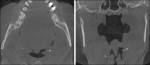

Below, we report the prevalence of incidental findings in a series of 561 CBCT scans acquired over a period of 18 months. All scans were made with the same CBCT scanner (GALILEOS, Dentsply Sirona, www.sirona.com) and a fixed FOV (15 cm x 15 cm) for routine dental assessment or dental implant placement. All scans were reviewed by a maxillofacial radiologist and a written report was generated and maintained in the patients’ dental records. The incidental entities found were categorized by means of significance based on the need for periodic evaluation or to refer the patient to a different clinician to address the incidental pathological entity. The most frequently met incidental entity in our review was a deviated nasal septum (83.1% of the cases reviewed). This is considered an abnormal condition or developmental anomaly in which the nasal septum is not centrally located in the nasal cavity but is shifted towards one side resulting in uneven nasal chambers. In most cases this is mild and requires no action. In some cases this is rather severe and may result in significant narrowing of the nasal passageways and thus difficulty in breathing (Figure 1).